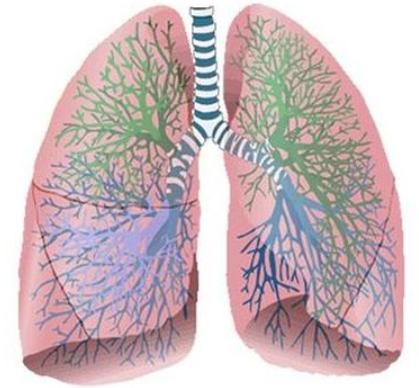

Здоровье дыхательной системы: бронхи и легкие